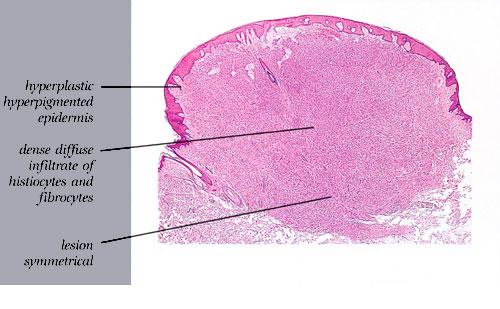

The overlying epidermis is usually acanthotic. Pseudoepitheliomatous hyperplasia and a basaloid proliferation may be noted. The hyperplasia may be caused by the action of fibroblasts on epidermal keratinocytes.23  Basal cell carcinomas occurring upon a dermatofibroma have been reported. Increased pigment may be seen, which may be iron or melanin. Most lesions display a grenz zone of normal papillary dermis overlying the tumor.

The bulk of the tumor is within the mid dermis where no capsule is present and the periphery of the lesion blends with the surrounding tissue. Whorling fascicles of a spindle cell proliferation with excessive collagen deposition are characteristic. At the periphery, the spindle cells characteristically wrap around normal collagen bundles (see the images below). Occasionally, melanocytes have been reported to be interspersed amongst the spindle cells.24